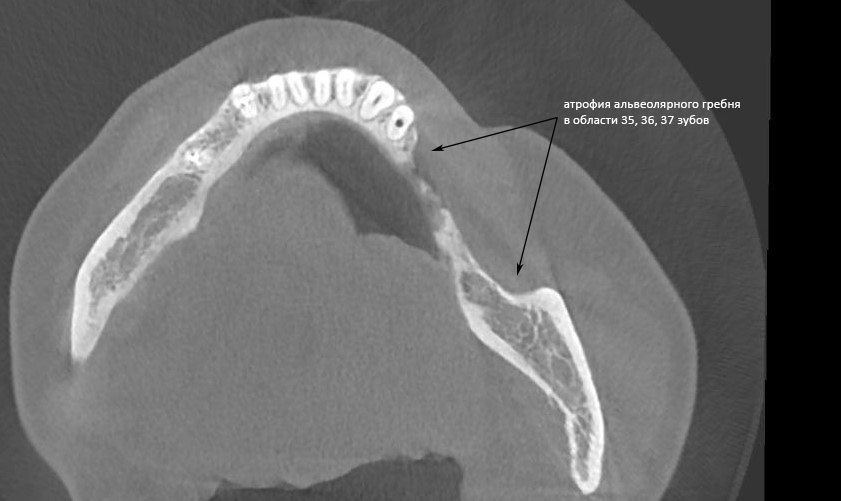

Простой. Надежный. Дешевый. Способ остеопластики.